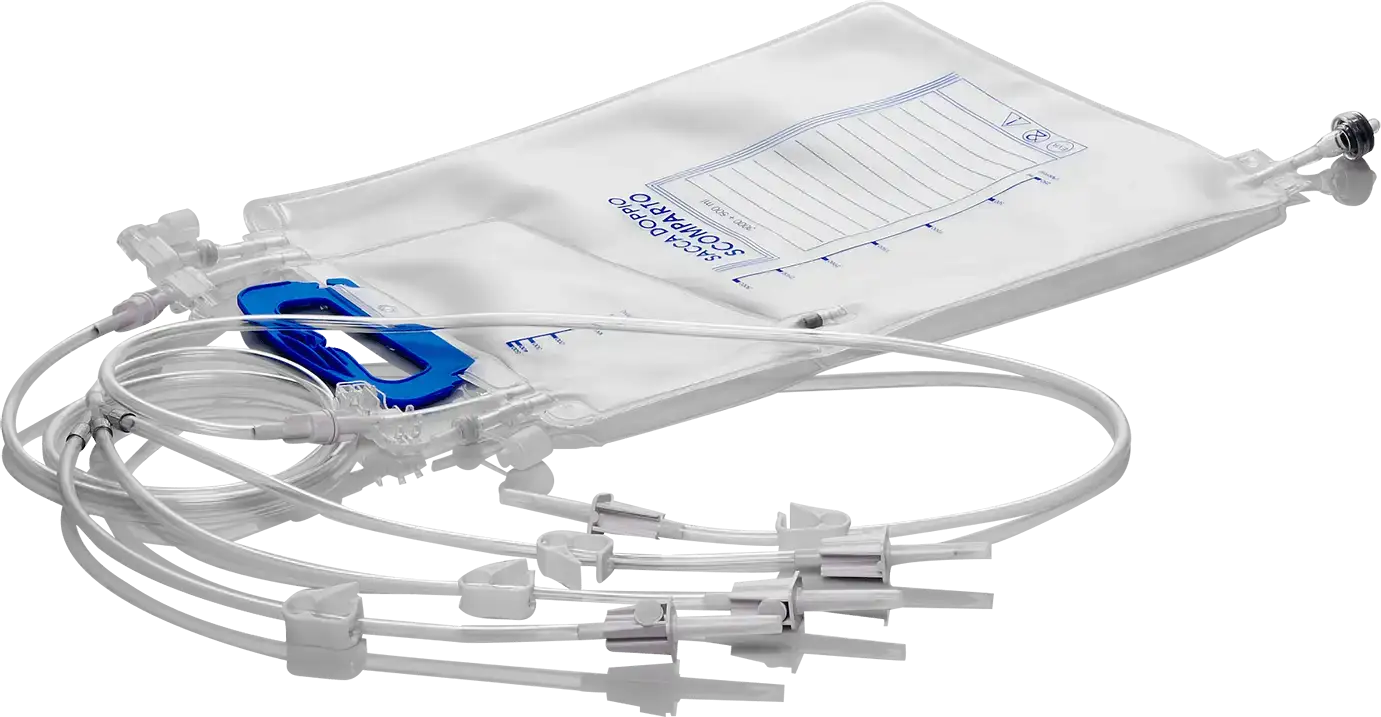

The perfect partner in the production of TPN, blood treatment, drainage and single use bags.

Valmed srl is the ideal partner, guaranteeing experience and know-how in the production of finished or semi-finished medical devices.